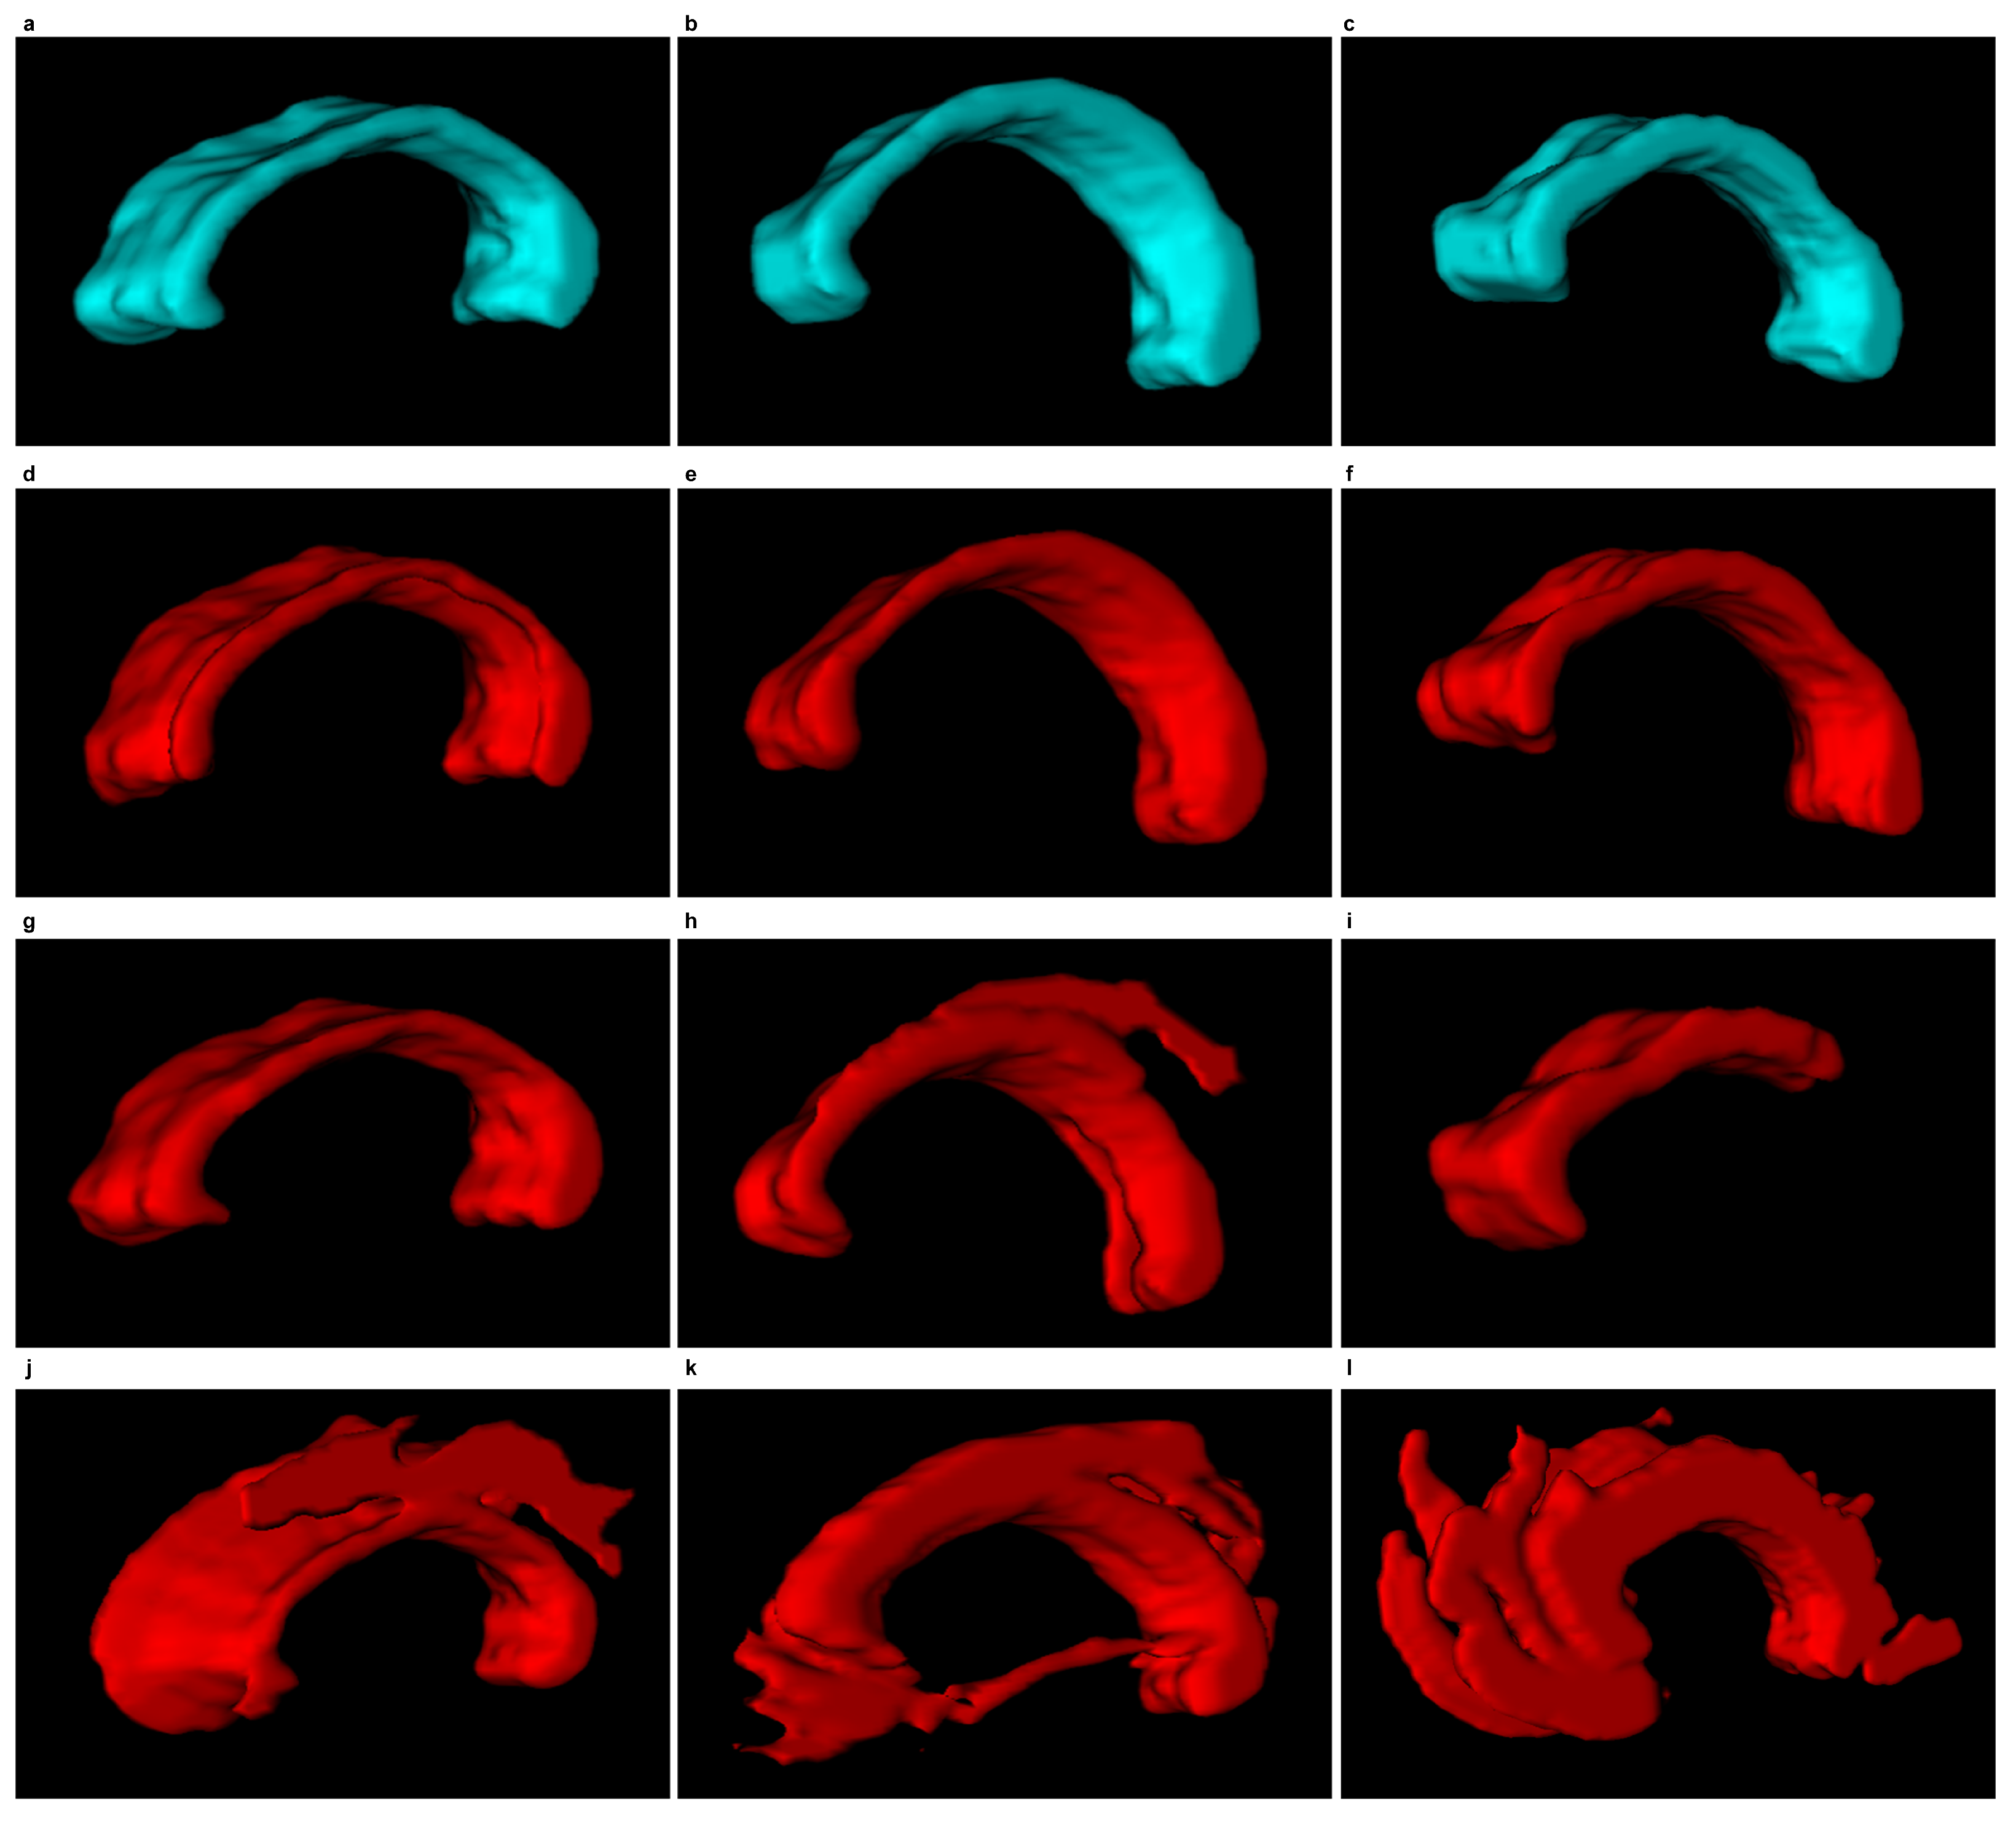

Figure 12 and Figure 13 demonstrate examples of 3D CC models produced using the segmentations obtained. The wrong segmentation in the plane makes the 3D models wrong as well. This is illustrated by examples from Figure 12h–l and Figure 13h–l.

Figure 12. 3D CC models (sagittal view) based on the segmentations produced and the subsequent 3D reconstruction. First column: ‘miriad_234_AD_M_03_MR_2’, second column: ‘miriad_244_AD_F_01_MR_2’, third column: ‘miriad_257_AD_F_05_MR_1’. First row: a model produced based on a segmentation manually traced by a physician ( E 1 ), Second row: with EM; Third row: with DRLSE. Fourth row: SBGFRLS.

Figure 13. Inverted 3D CC models, continued from Figure 12.